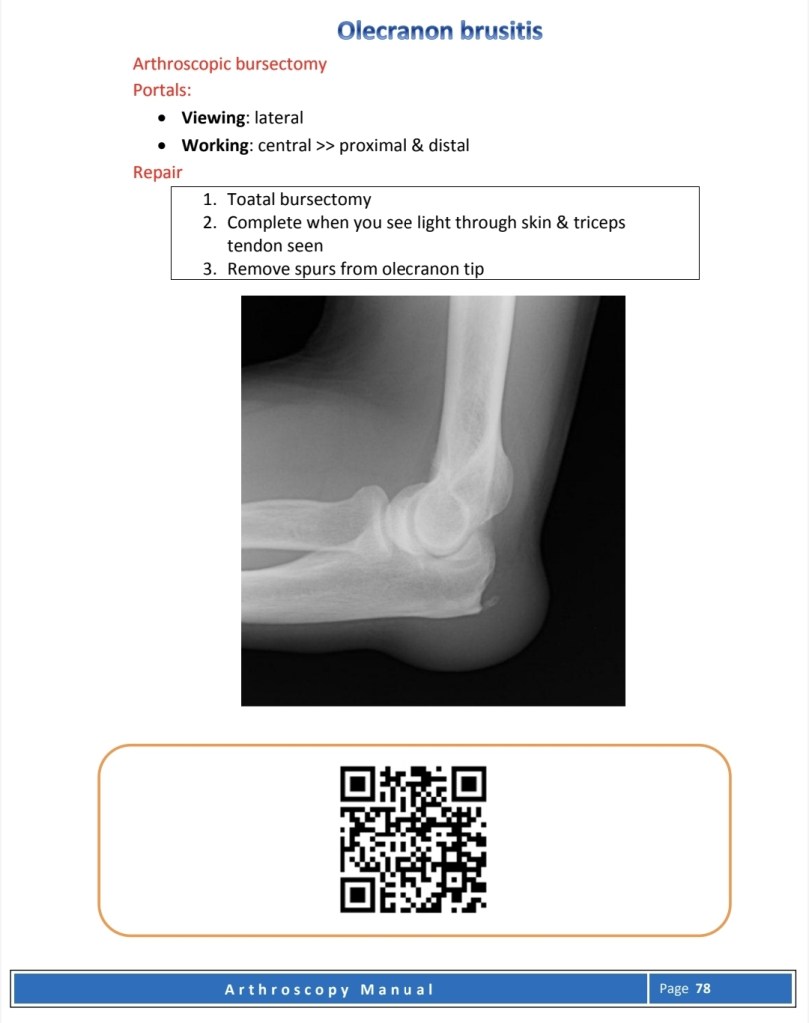

Other Elbow problems

Elbow procedures